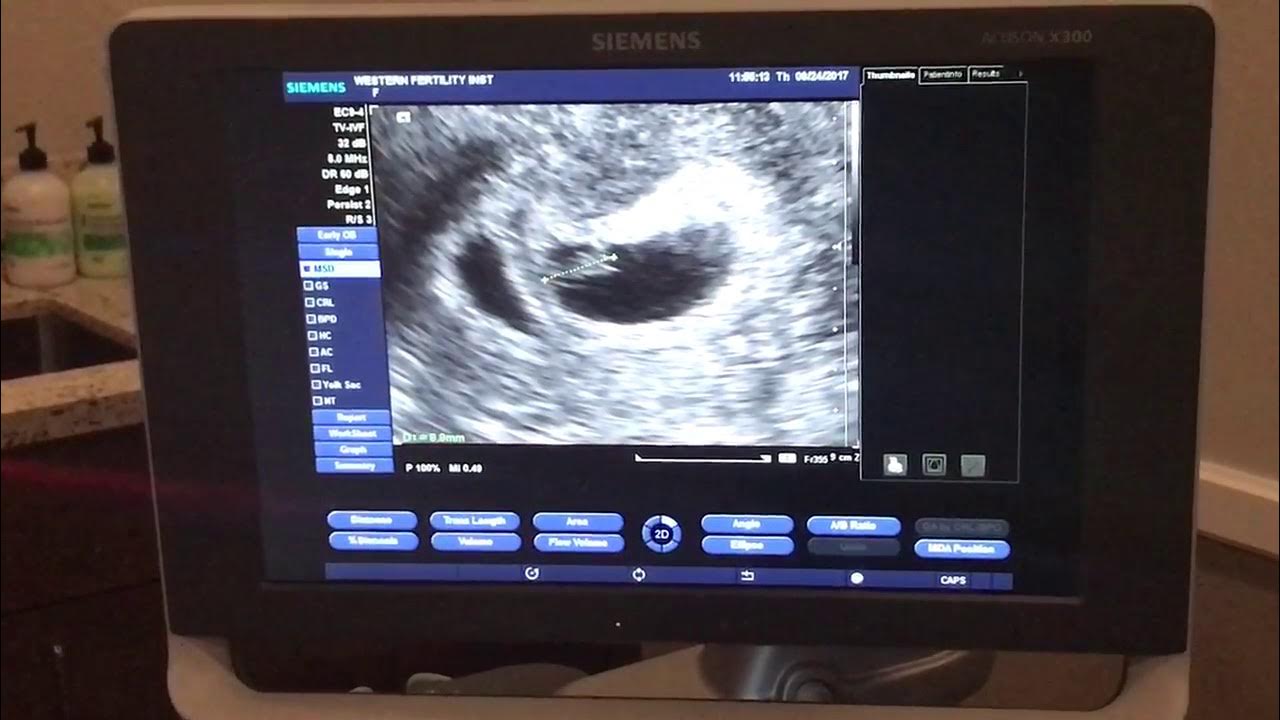

Pregnancy ultrasound at 8 to 9 weeks with heart beat YouTube Video Of Baby Heartbeat At 8 Weeks At 8 weeks pregnant, you are halfway through your first trimester. The first time we heard our baby's heartbeat at 8 weeks. At 8 weeks pregnant, you may hear your baby’s heartbeat at your first prenatal appointment. Learn how fetal heart rate changes throughout pregnancy and what is normal for each week of gestation. Learn how to prepare for a. Video Of Baby Heartbeat At 8 Weeks.

8 weeks Pregnant Ultrasound with heartbeat YouTube Video Of Baby Heartbeat At 8 Weeks Learn what you can see on the scan, how it's done, and what to do if you can't. Learn about the normal fetal heart rate range by week, from 6 to 32 weeks, and the methods to detect and hear the baby's heartbeat. Learn how to prepare for a transabdominal or transvaginal scan, what to see on the image, and. Video Of Baby Heartbeat At 8 Weeks.